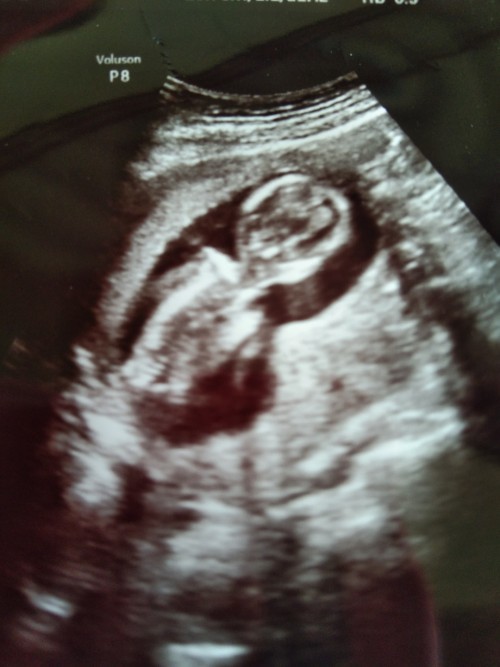

ตอน13w+6ค่ะ

เหนชัดมากคะ